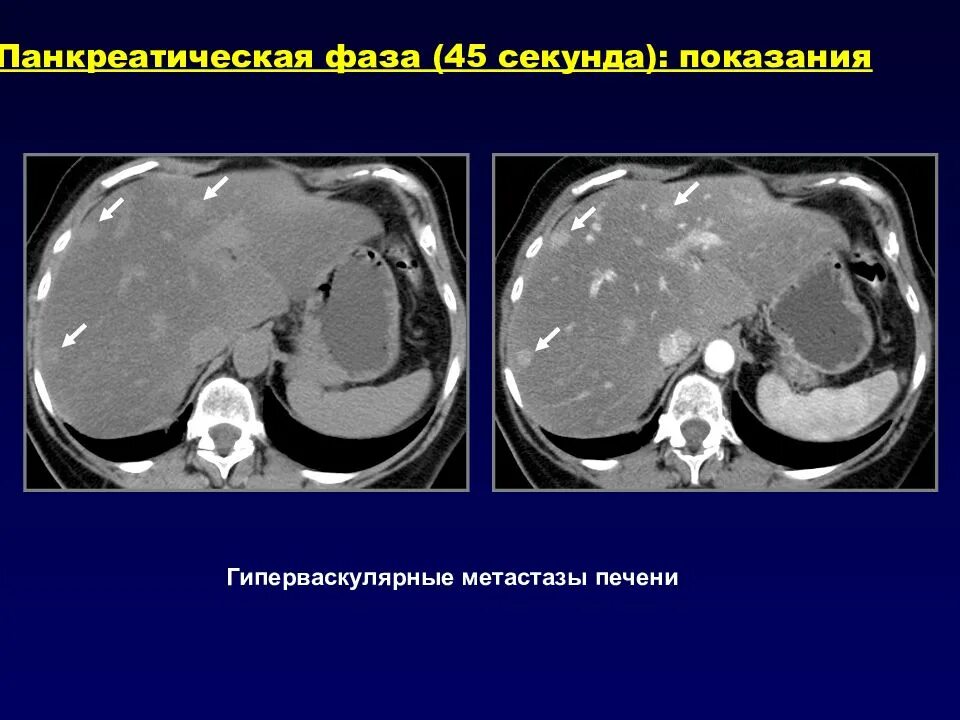

Образования печени кт